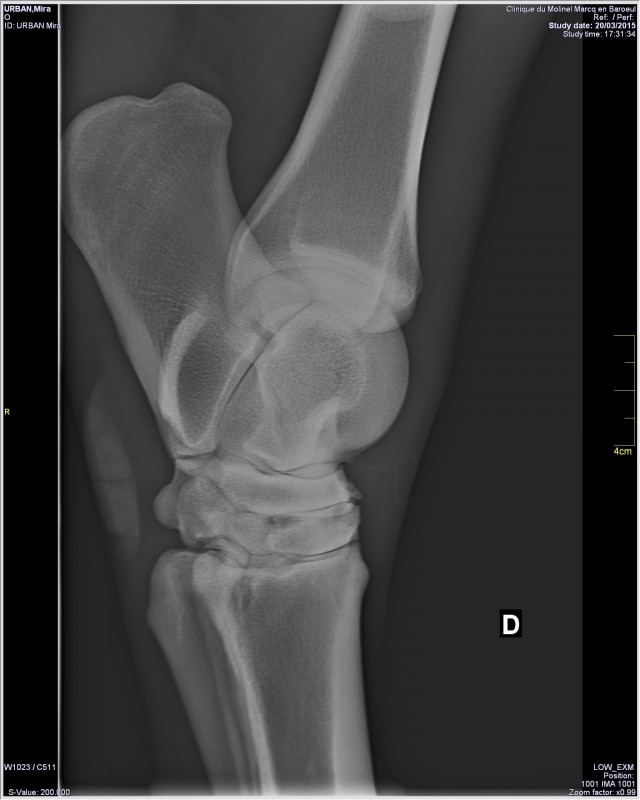

Pour l'infiltration, je l'ai fait inflitré au jarret le plus atteint.

Et bien ça l'a énormément soulagé, plus de craquements à ce jarret, plus de gêne etc.